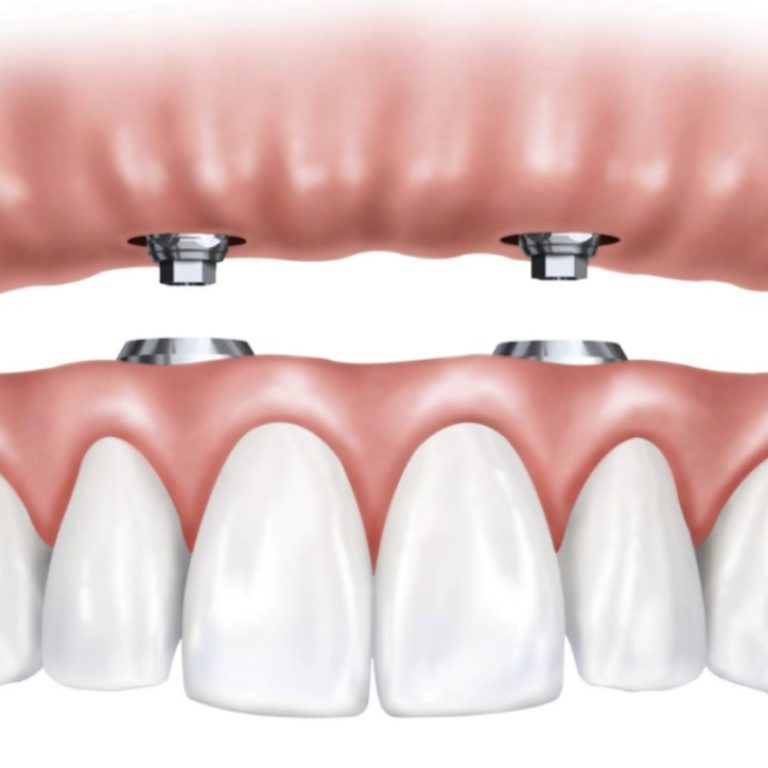

Introducing All-on-4 Implants in Sydney: A Life-Changing Full-Arch Solution For many people, losing multiple teeth—or facing the possibility …

Dental Implant vs Bridge vs Denture: Which Tooth Replacement Is Right for You? Losing a tooth isn’t just …